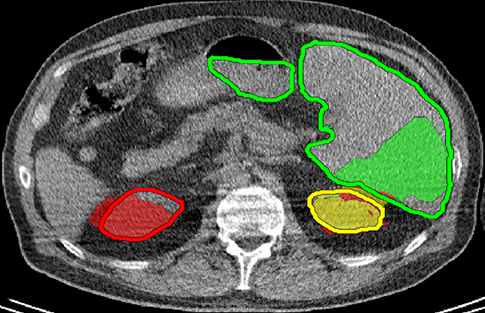

We applied our method on PET-CT scans of three different subjects to segment their liver, left kidney, right kidney and the background. Although we applied our method and Potts model on the 3D volumes we only show the results on a few representative slices from each volume in Fig.11. Also, the results of different methods for each subject were computed using the same smoothness. We can see from the last two rows which compare our method to Potts, using Hedgehogs constraints enabled us to avoid geometrically incorrect segmentations, e.g. one liver inside the other (last-row middle), or parts of left kidney is between the right kidney and liver (last-row right). Furthermore, for test subjects 1 and 2 the kidneys and background were poorly segmented by Potts model, e.g. most of the kidneys were segmented as background for test subject 1. Potts poor performance is due to the large overlap between the kidneys and background color models. This overlap resulted in an in-discriminative data term for Potts to properly separate them. This issue becomes worse in iterative frameworks where color models are re-estimated based on current segmentation. To be specific, if at any iteration Potts model resulted in a bad segmentation then re-estimating the color models will bias them towards the bad segmentation and subsequent iterations worsen the results. Comparing our results for subjects 1 and 2 to Potts model shows that our method is less prone to the aforementioned issue as we forbid undesirable segmentations, i.e. those that do not respect shape constraints.

| Subject 1 | Subject 2 | Subject 3 | |||

| Our method (Hedgehogs Shapes + Potts) | ![]() |

|

Potts |

For quantitative comparison, Table 1 lists for each organ of a subject the Score, Precession and Recall measures of our method and Potts model where For the kidneys, our method clearly out performed Potts model, e.g. note Potts model poor precision/recall for subjects 1 and 2. For the liver, both methods performed comparably.